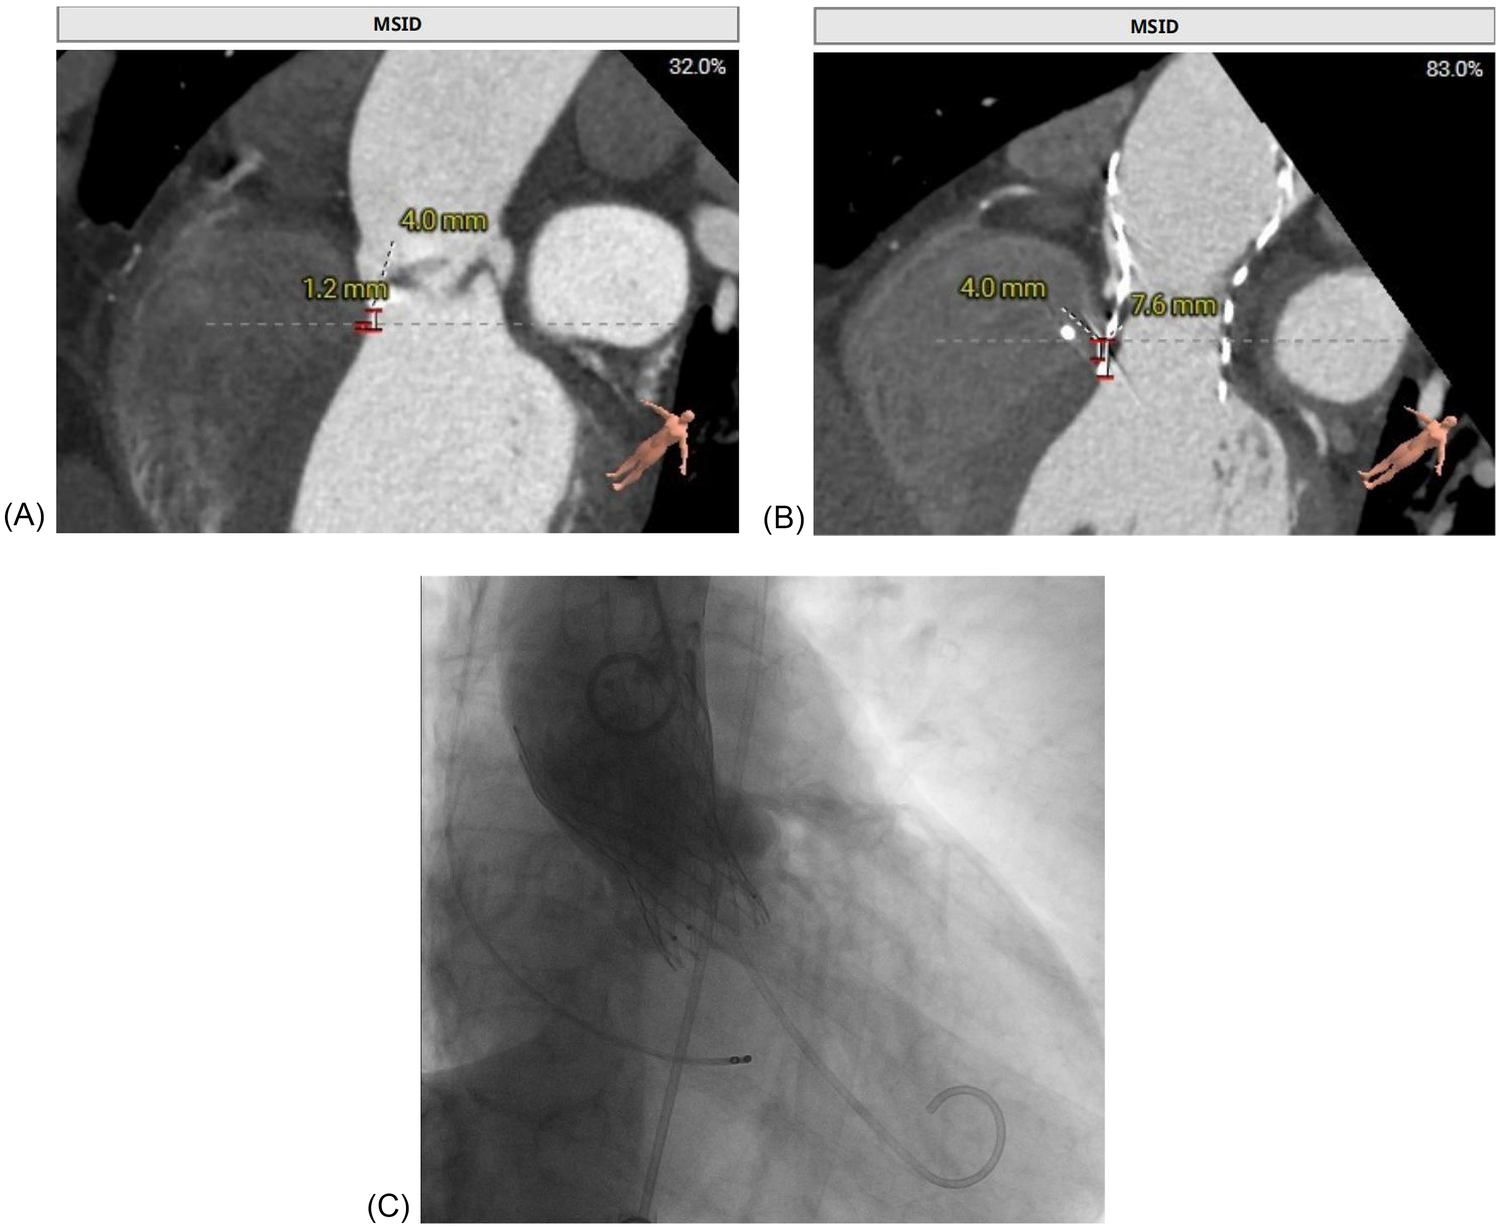

The patient's presentation with progressive exertional dyspnea and tachycardia was consistent with decompensated heart failure in the setting of severe aortic stenosis. Baseline echocardiography, as detailed earlier, confirmed severe low-flow, low-gradient aortic stenosis with a reduced systolic function. Baseline ECG revealed sinus tachycardia with repolarization abnormalities (ST-segment depression and biphasic/inverted T-waves), fragmented QRS features, and left atrial enlargement (P mitrale) (Figure 2A). Given the patient's age, hypertension, and family history, ischemic cardiomyopathy was considered. Coronary CTA and intraprocedural coronary angiography demonstrated coronary artery disease without vessel occlusion (LM/LAD 60%–70%, LCX 50%, RCA without significant stenosis), and TTE did not show stenosis-correlated regional wall motion abnormality—making an ischemic etiology less likely as the primary driver of reduced LVEF at presentation. Preoperative CT angiography demonstrated a short membranous septum measuring 4.0 mm and a membranous septum–annulus distance of 1.2 mm, findings that placed the patient at an elevated risk for postprocedural conduction abnormalities (Figure 1A). Preprocedural assessment suggested Sievers type I functional bicuspid anatomy with left–right fusion and a heavily calcified raphe. In this context, a balloon-expandable valve was considered but was felt to carry a higher risk of annular/root injury given the calcific burden. Therefore, based on anatomical feasibility and institutional experience, a self-expanding platform was selected. Holter monitoring on postoperative day 2 revealed stable electrical activity without immediate, high-grade conduction disturbances.

Figure 1

Multimodal imaging of a patient with delayed atrioventricular block after TAVR replacement. (A) Preprocedural CT demonstrated a short membranous septum (4.0 mm) and a membranous septum–annulus distance of 1.2 mm, consistent with a high conduction risk. (B) Post-event CT showed further valve expansion, with a frame depth of 7.6 mm at the membranous septum plane and 9.8 mm at the non-coronary cusp, consistent with progressive compression of the conduction system. (C) Fluoroscopic image during transfemoral TAVR, confirming deployment of the self-expanding Qiming L26 prosthesis at a depth of approximately 5 mm.

The patient was admitted for temporary pacing after a diagnosis of complete AV block with a ventricular escape rate of 30 bpm. Despite initial temporary pacing, the block persisted, and after 5 days, a dual-chamber PPM was implanted. A dual-chamber device was chosen over a single-chamber system to preserve atrioventricular synchrony and optimize hemodynamic performance in patients with preexisting left ventricular dysfunction. Conduction system pacing (His-bundle pacing or left bundle branch area pacing) was considered to better preserve ventricular synchrony; however, given the limited local experience with these techniques at the time and the need for prompt, reliable therapy in symptomatic complete AV block, we selected a conventional dual-chamber system with RV septal pacing. Fluoroscopic imaging during TAVR confirmed deployment of the self-expanding Qiming L26 valve at a depth of approximately 5 mm (Figure 1C). Post-implantation TTE showed stable prosthetic valve function, and the patient was discharged in good condition on postoperative day 3.

Our institutional post-TAVR follow-up plan was scheduled at 1, 3, 6, and 12 months with ECG and echocardiography; however, adherence to this plan was incomplete. At the 1-month telephone follow-up, we advised in-person reassessment, but the patient declined the ECG/TTE because he felt well. At the 8-month follow-up in May 2025, TTE demonstrated resolution of the paravalvular leak, and the patient remained in sinus rhythm at 75 beats per minute (Figure 2B). On July 9, 2025, a community ECG revealed a new 2:1 AV block with a ventricular rate of 41 bpm (Figure 2C). As the patient reported no marked symptoms at that time and did not appreciate the risk, he did not seek urgent specialist assessment at that time. Three weeks later, on August 7, 2025, he presented with progressive fatigue and dizziness, and a hospital ECG confirmed complete AV block with a ventricular escape rhythm of 30 bpm (Figure 2D). Repeat CT at this time showed progressive valve expansion, with a frame depth of 7.6 mm at the membranous septum plane and 9.8 mm at the non-coronary cusp, consistent with mechanical compression of the conduction system (Figure 1B). Device interrogation confirmed appropriate dual-chamber pacemaker function, and the patient reported complete symptomatic recovery, resuming normal daily activities with stable prosthetic valve performance.